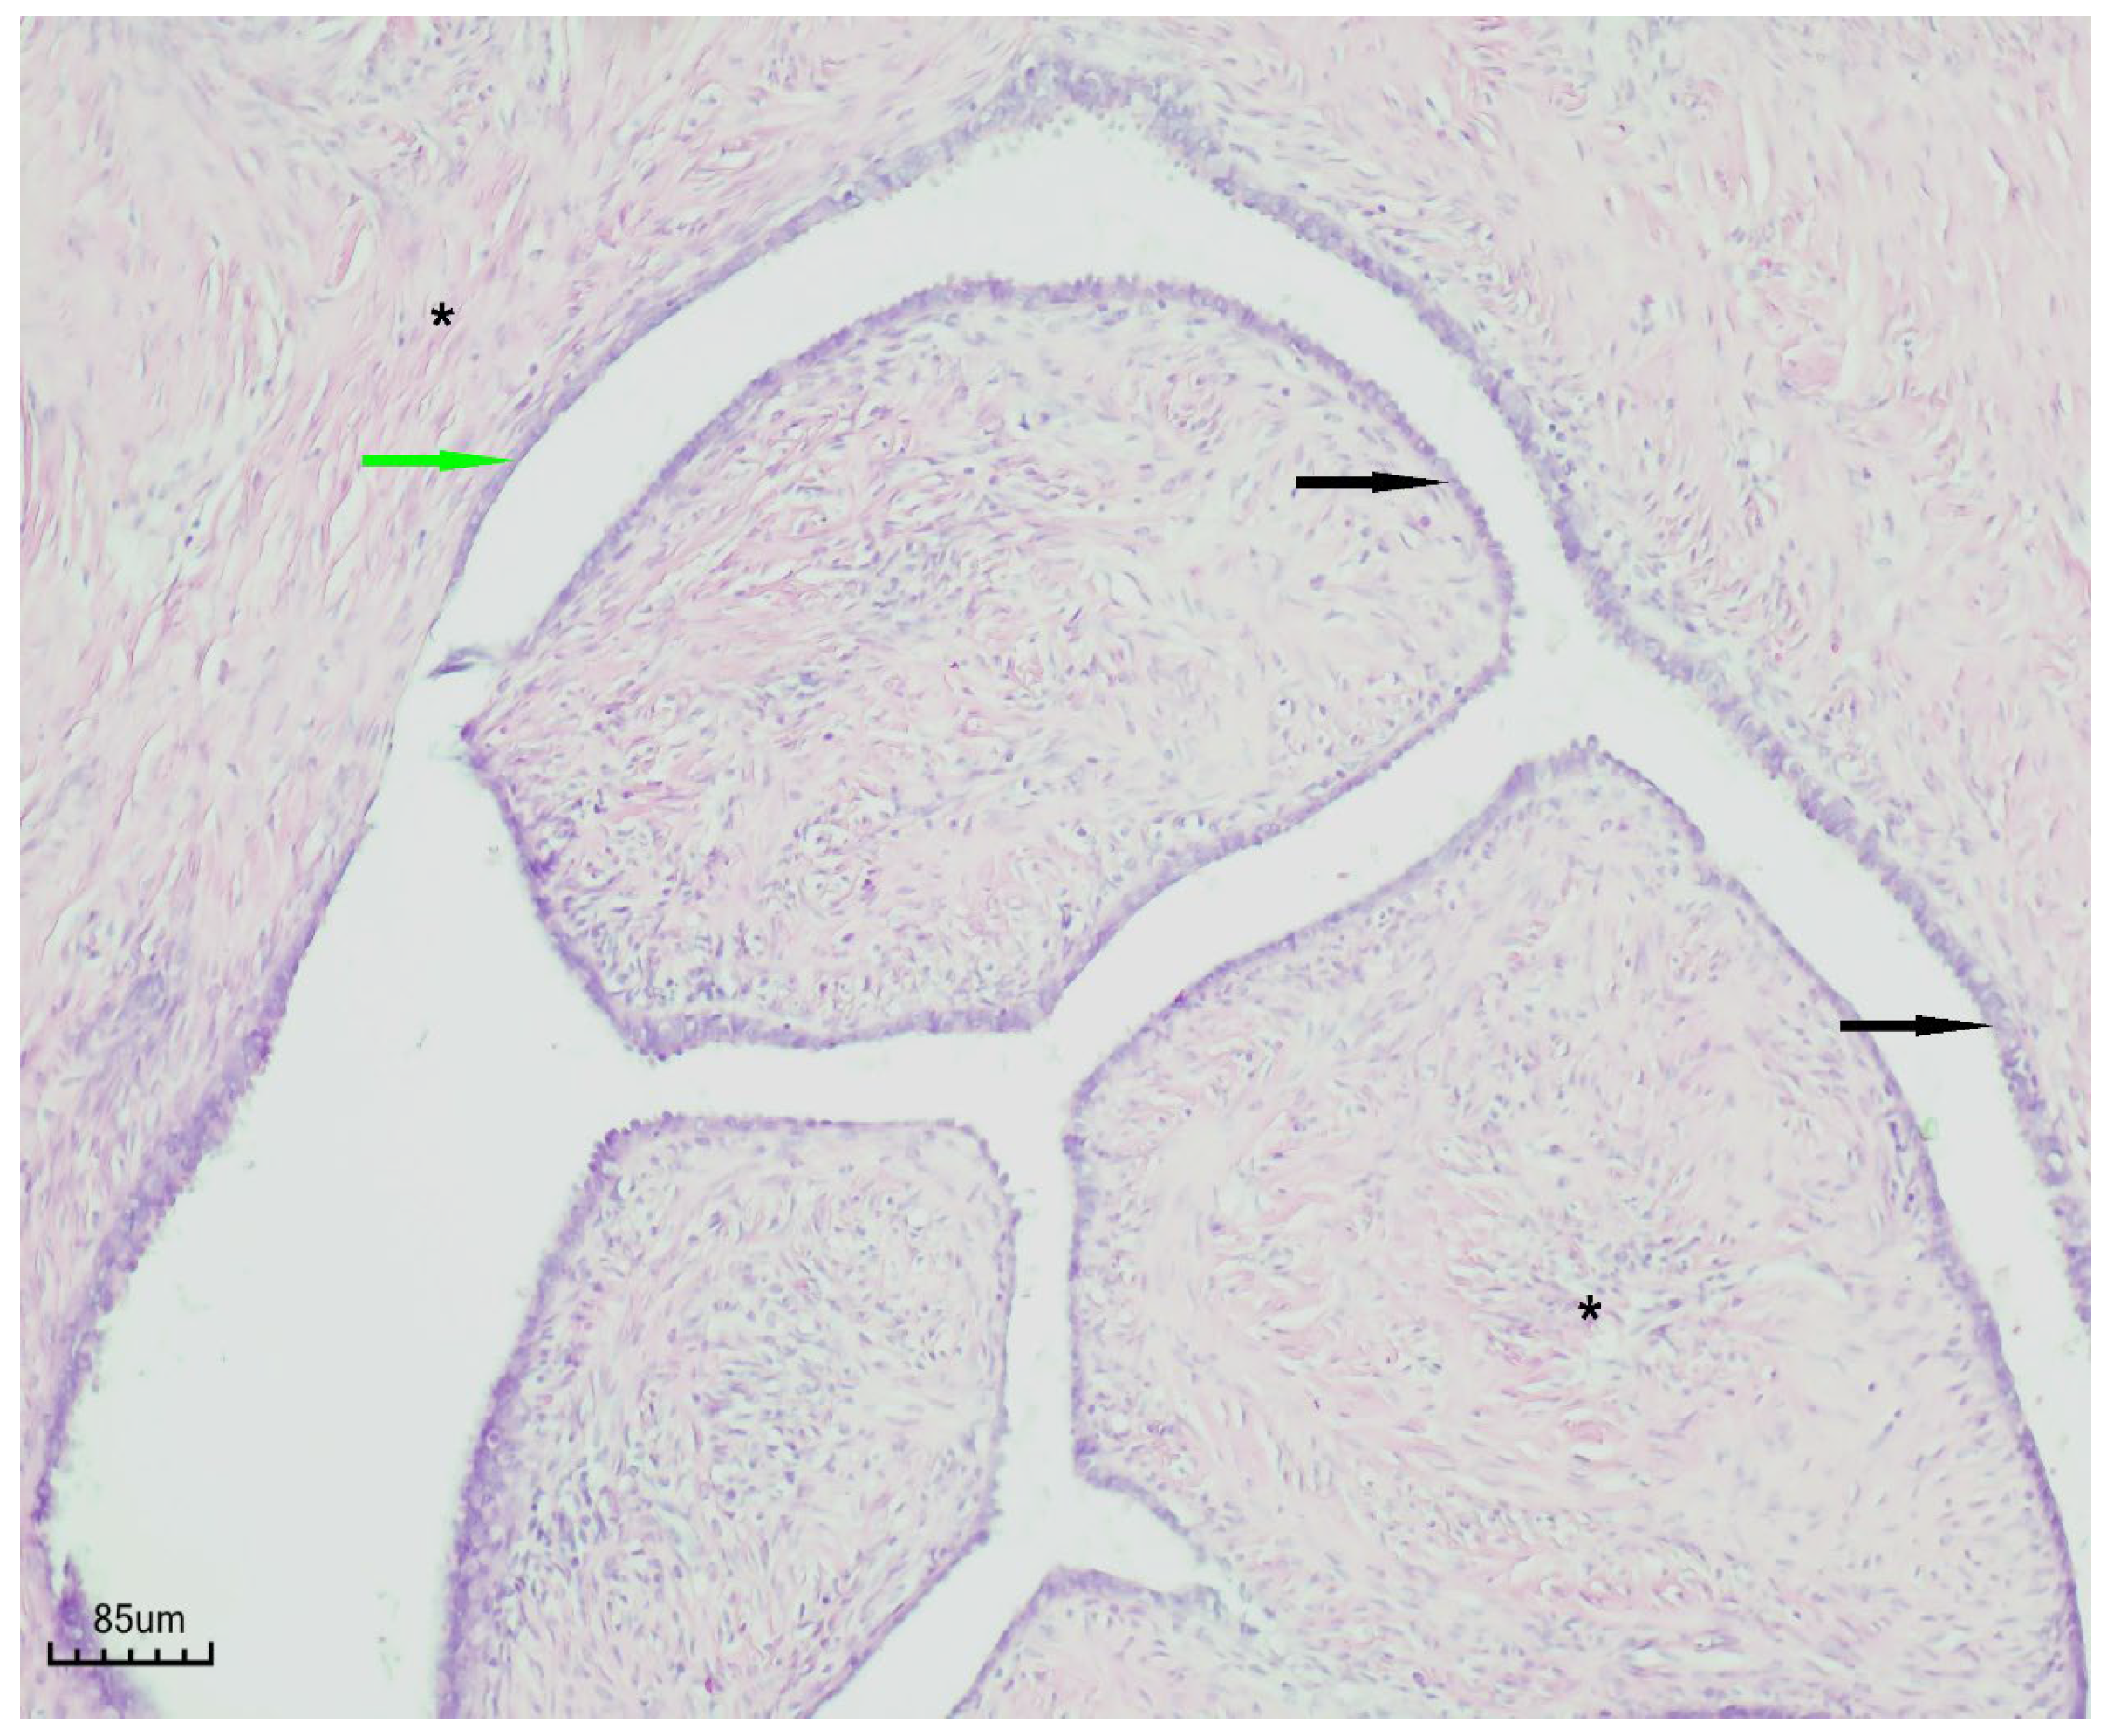

The patient was first evaluated using gynecologic ultrasound, including transvaginal sonography (TVS), which is the first-line diagnostic tool for adnexal masses in clinical practice. Transvaginal sonography (TVS) revealed a complex left adnexal mass with cystic morphology, showing well-defined borders and thin internal septations (Figure 1). Subsequently, magnetic resonance imaging (MRI) was performed as a complementary investigation to provide additional characterization of the lesion and to assist in the differential diagnosis with borderline or malignant ovarian tumors.

Figure 1. Transvaginal sonography (TVS) of the left adnexa ( orange arrow) demonstrating a complex ovarian cyst with cystic morphology, thin internal septations, and well-defined borders.

Figure 6. Papillary serous cystadenofibroma (H&E staining, ×100). The cystic wall is indicated by the green arrow, the simple-to-pseudostratified epithelium by the black arrow, and the fibrous stroma by the black asterisk.